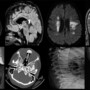

Figure A – D:

Axial FLAIR (A) and sagittal FLAIR (B) sequences of the brain show asymmetric confluent T2/FLAIR hyperintensities involving frontoparietal white matter (red arrows) and splenium of the corpus callosum (yellow arrow). Thinning of the posterior part of the body of the corpus callosum is seen (purple arrow). These signal changes demonstrate diffusion restriction on axial DWI sequence (C) (white arrows). Coronal T2 sequence of the brain (D) shows T2 hyperintensities extending along the bilateral corona radiata and internal capsule (R>L) (extension along the corticospinal tracts) (black arrows). No enhancement was seen on post-contrast sequences. The sparing of the subcortical U fibres was noted. No signal changes in the bilateral basal ganglia, brainstem and cerebellum were seen. Note is also made of diffuse generalised cerebral atrophy and ventricular enlargement, disproportionate to age.

Figure E- H:

Coronal T2 of the orbit (E) shows atrophy of the left optic nerve (red arrow). Axial CT in the bone window (F) shows diffuse sclerosis of the skull base (yellow arrows). Lateral radiograph of lumbo-sacral spine (G) demonstrates platyspondyly (purple arrow). AP radiograph of the left wrist (H) shows widened metaphyses of the distal ends of the ulna and radius, and metacarpals (green arrows).